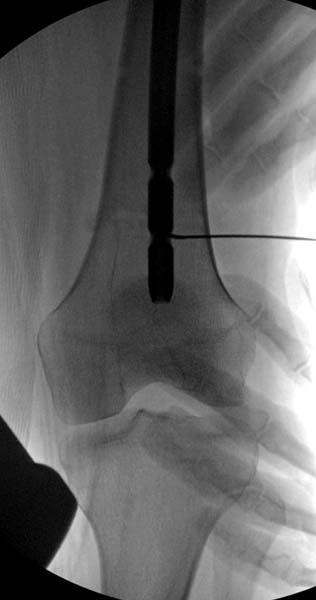

Больная стабильная после хирургических мероприятии и получив добро, приступили к закрытому вправлению таранной кости с укладкой наружного фиксатора. Затем укладка больную на бок и открытый остеосинтез перелома-вывиха головки бедра.

По характеру повреждения головка находится сзади и напрашивается задний Кохер-Лангенбек доступ, но в заднем доступе имеется риск повреждения магистрального кровоснабжения головки a. circumflexa. Более щадящая trochanteric flip (digastric osteotomy) сохранит кровоснабжение и дасть возможность работу при вывихнутом суставе.

После спадения отека на стопе произведена фиксация тарана. Кстати, коллеги пересмотрели первоначальную консультацию по позвоночнику и на двух уровнях провели фиксацию. Из-за длительного постельного режима без нагрузки таз не стали оперировать...